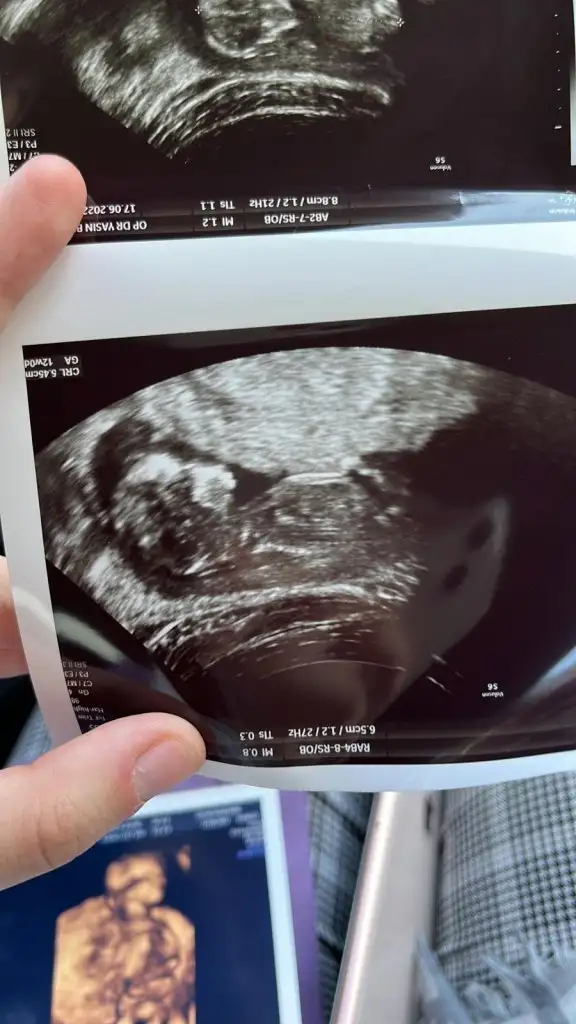

Paşa gibi14+1 karnimdan ultrason tekrar bakabilir misin canım

prenses gibi12+0 canım bakabilir misin

Teşekkür ederimprenses gibi